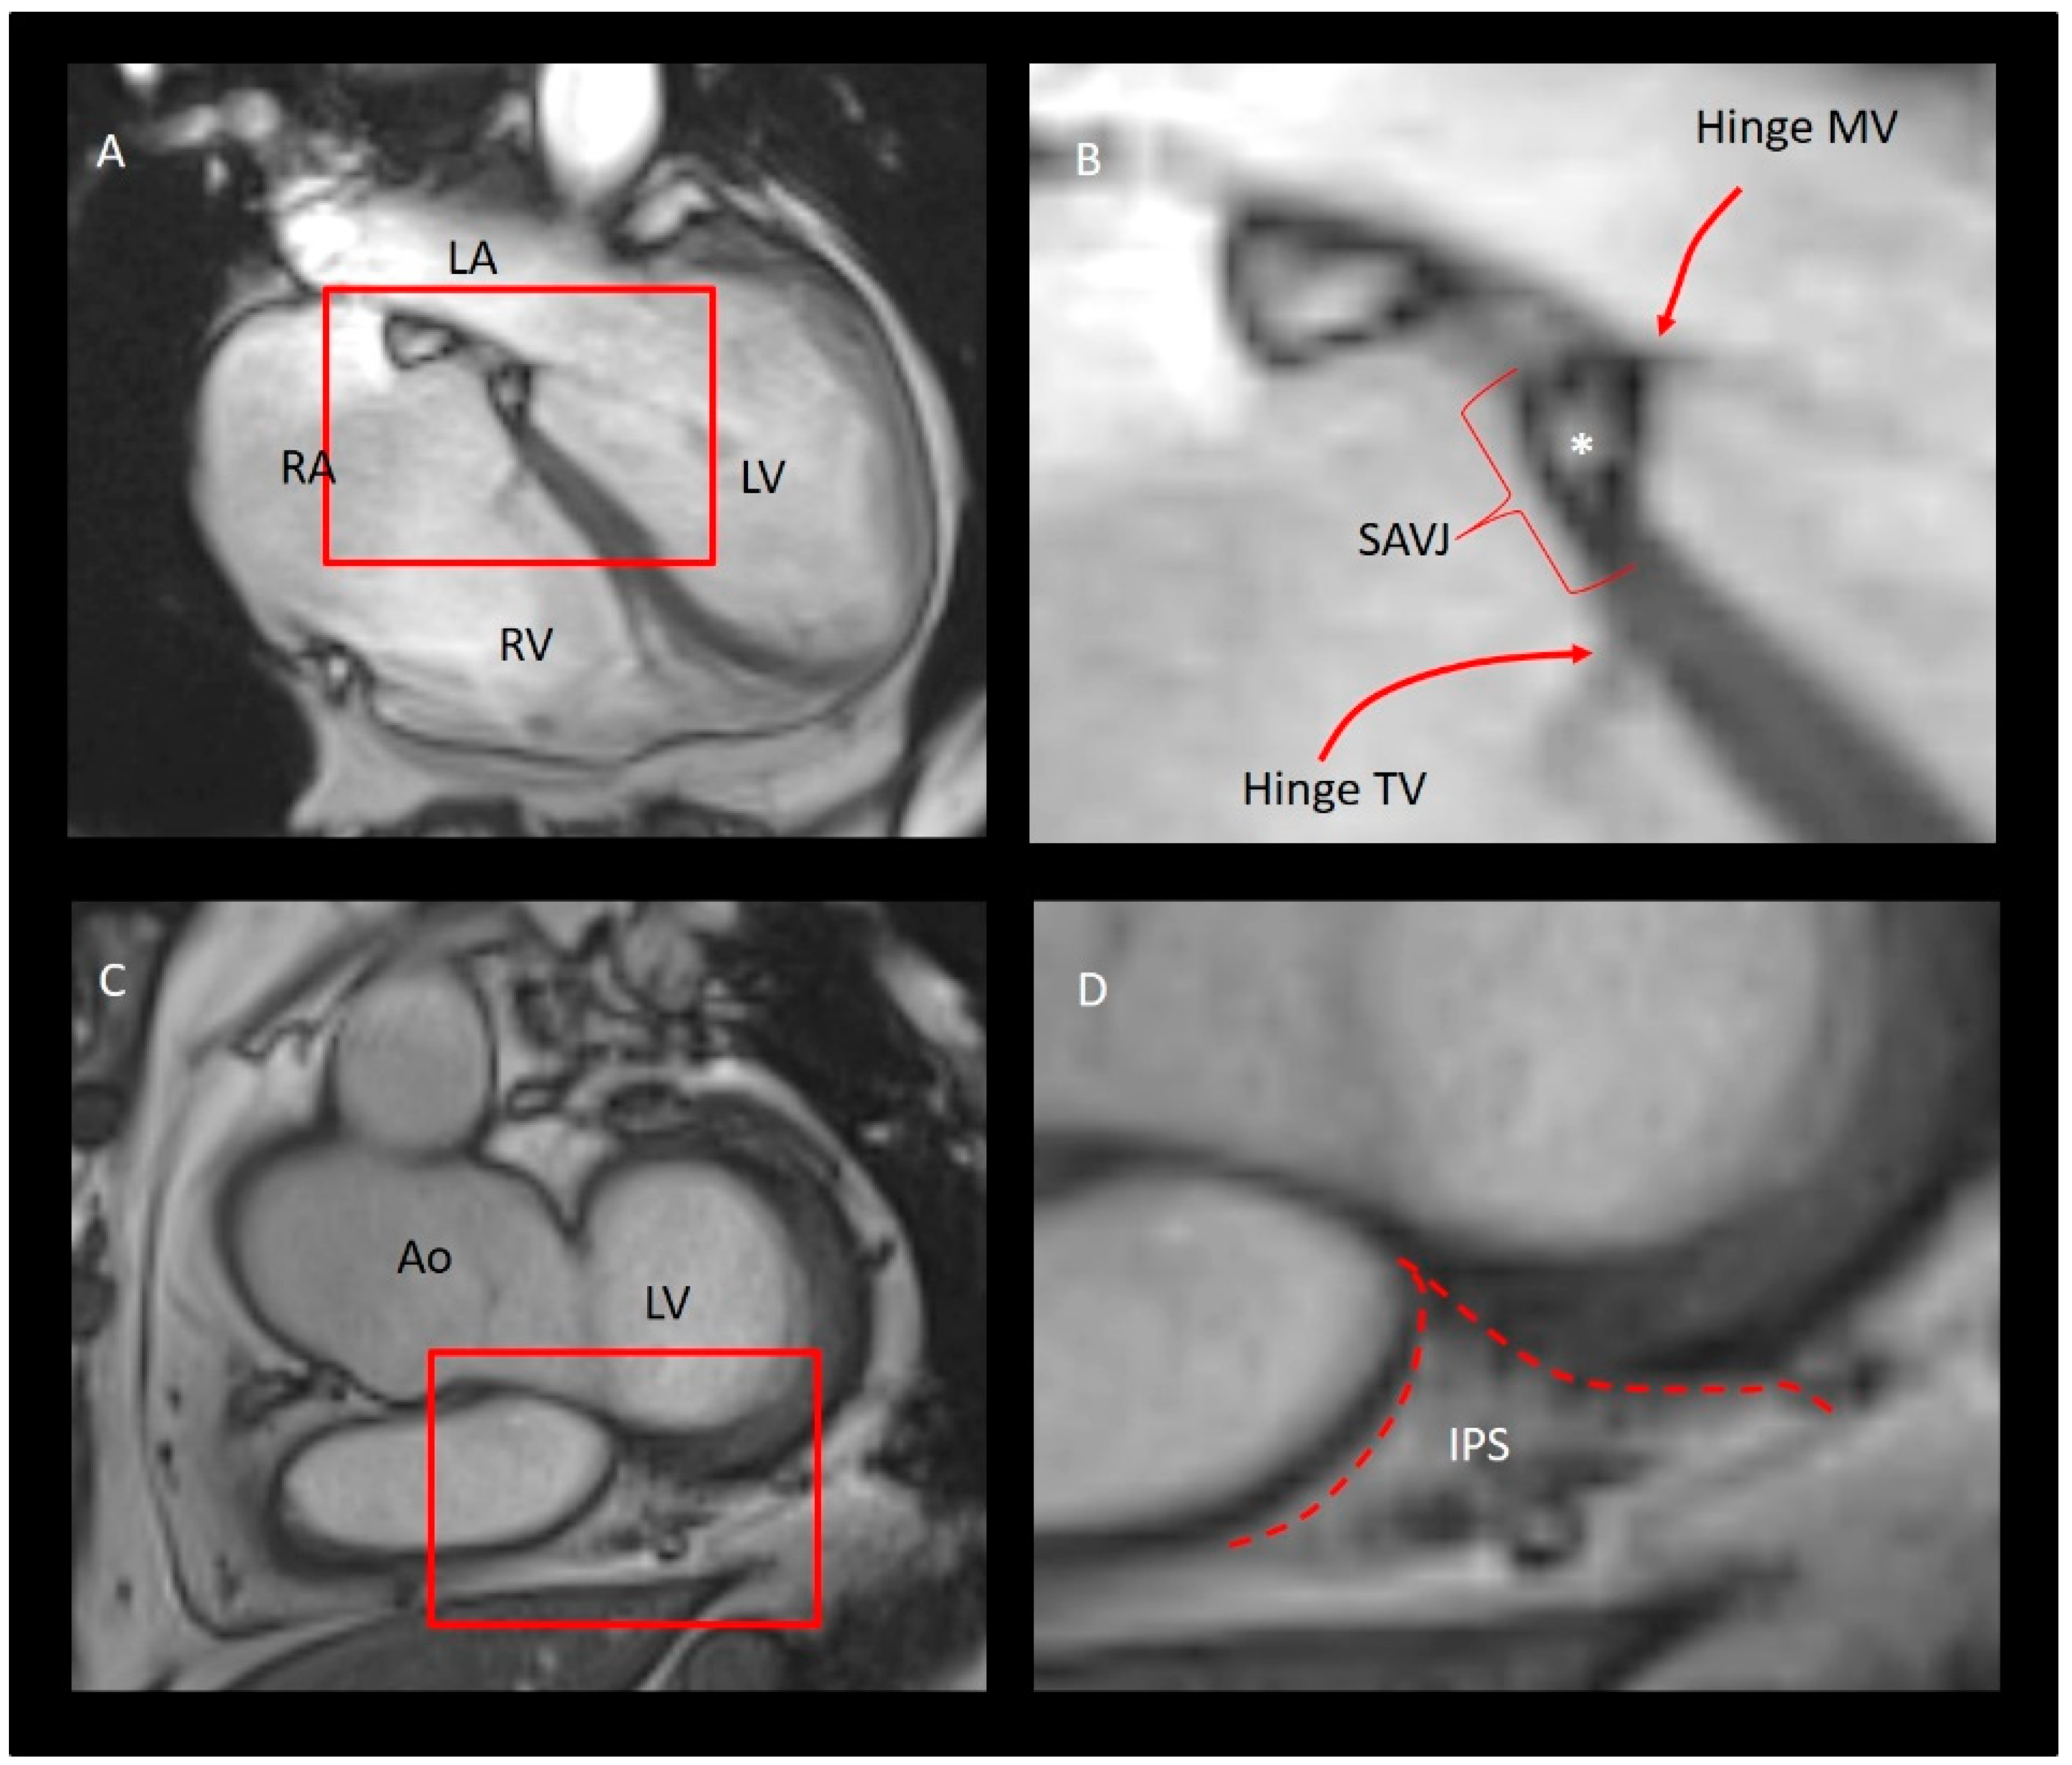

The “Mural” Annulus

4. The “Septal” Annulus

5. Physiological and Physiopathologic Consequences of the Annular Structure